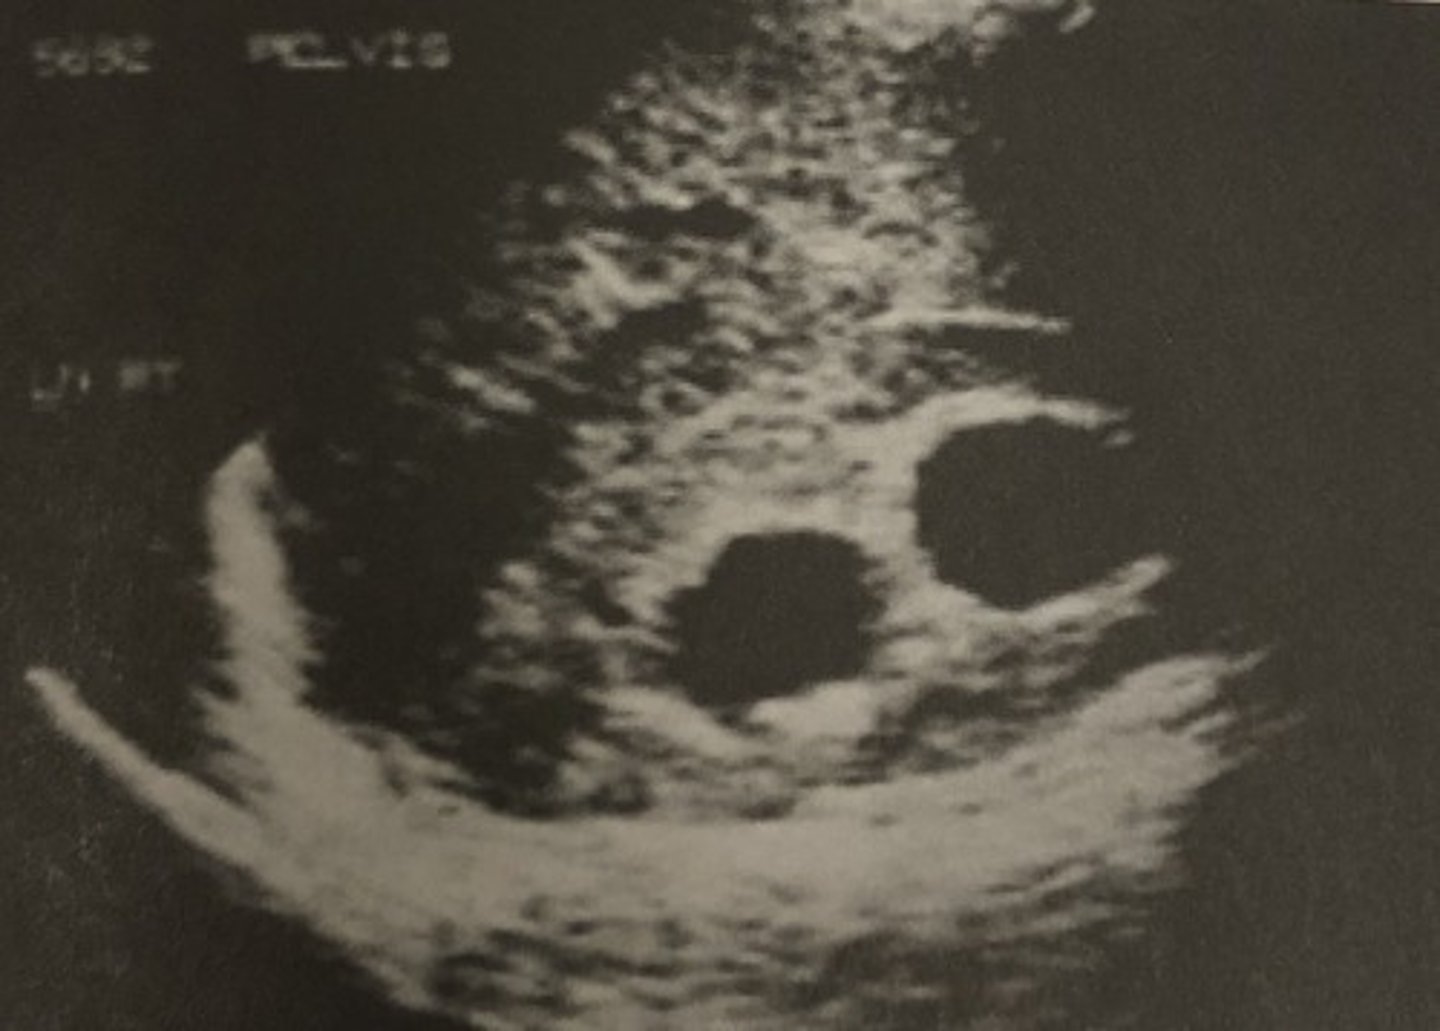

A. Pelvic ascites

639. On bimanual pelvic examination, the clinician cannot palpate the uterus or ovaries. This image suggests:

B. Atrophied organs

C. Bowel obstruction

D. Patient obesity

E. Constipation

A. Slice-thickness artifact

640. The arrow in the image in question 639 is pointing to:

B. Bowel

C. Side lobe artifact

D. Debris

E. Septation